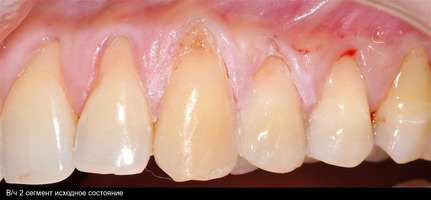

В области от 1.6 до 2.6 и от 3.6 до 4.6 все зубы имеют некариозные поражения разной степени, такие как эрозии эмали и клиновидные дефекты, вовлекающие в процесс ткани эмали и дентина. Подвижности зубов не выявлено (рис. 1а-е) [9].

При анализе и описании компьютерной конусно-лучевой томографии (рис. 2а-г) была выявлена генерализованная первичная дегисценция вестибулярной пластинки кости от 1/2 до 3/4 длины корней зубов, зубной ряд целостный, все зубы витальны, кариозных поражений нет. Тип кости 1-2 (Lechkolm и Zarb, 1983), первичная дегисценция вестибулярной костной пластинки превышает пределы возрастной атрофии.

Исходный диагноз: генерализованные рецессии десны 1 и 2 класса по Миллеру [7, 9, 10].